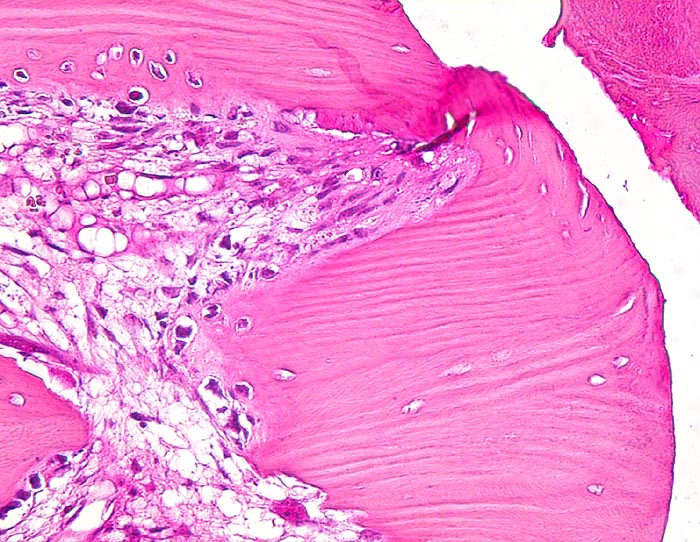

sekundäre Frakturheilung: Frakturspalt mit Kallus

Knochen, Rippe

Frakturspalt mit Fibrin. Devitalisierter ortsständiger Knochen mit leeren Osteozytenhöhlen begrenzt den Frakturspalt. Osteoklasten bauen das devitalisierte Gewebe ab. Granulationsgewebe im Markraum.

Konservativ behandelte Rippenfraktur nach Sturz vor einem Monat.

160